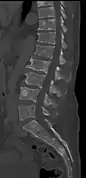

The diagnostic examination of a person with suspected multiple myeloma typically includes a skeletal survey. This is a series of X-rays of the skull, axial skeleton, and proximal long bones. Myeloma activity sometimes appears as "lytic lesions" (with local disappearance of normal bone due to resorption) or as "punched-out lesions" on the skull X-ray ("raindrop skull"). Lesions may also be sclerotic, which is seen as radiodense.[70] Overall, the radiodensity of myeloma is between −30 and 120 Hounsfield units (HU).[71] Magnetic resonance imaging is more sensitive than simple X-rays in the detection of lytic lesions, and may supersede a skeletal survey, especially when vertebral disease is suspected. Occasionally, a CT scan is performed to measure the size of soft-tissue plasmacytomas. Bone scans are typically not of any additional value in the workup of people with myeloma (no new bone formation; lytic lesions not well visualized on bone scan).

Pathological fracture of the lumbar spine due to multiple myeloma